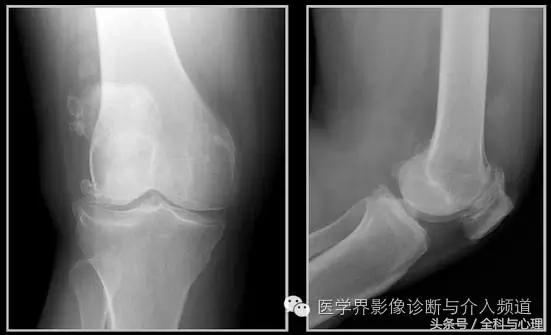

4、痛风石

为尿酸盐沉积形成,发生在关节周围软组织、包括韧带、肌腱、滑囊,眼、耳、鼻、喉、皮肤, 50%的钙化为X线平片可见。

痛风石,可见软组织肿胀及钙化灶。